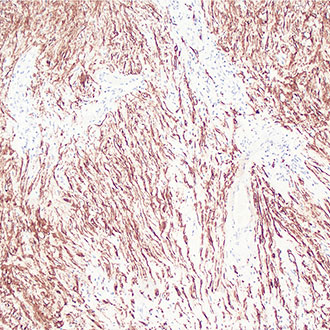

SMA

SMA -